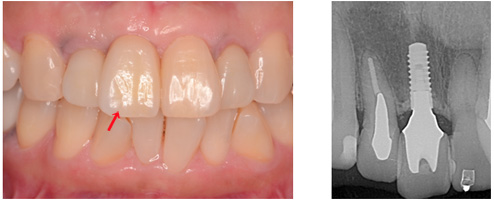

実際の治療 奥歯2本の症例

こちらの人工歯はセラモメタルクラウンですが、2本でトータル72万円でした

実際の治療 前歯1本

こちらの人工歯はジルコニアセラミッククラウンでトータル45万円でした

金額は2019年12月のものです